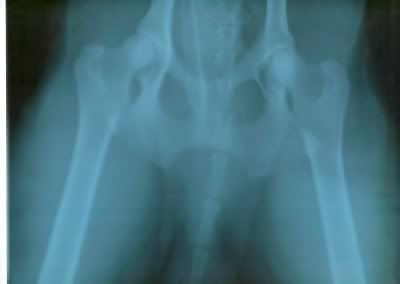

vanochtend heb ik bo zijn heupen op de foto laten zetten. heb het bij een da laten doen die ook officiele hd heupfoto's maakt. ik heb het niet officieel laten doen, maar gewoon voor mezelf of ik met de tijd in oostenijk een wandelvakantie kan gaan doen.

zijn heupen zagen er mooi uit er waren geen aanwijzingen voor heupdysplasie. de eerste foto was wat te licht en is dus over gedaan, op de eerste zijn zijn heupen wel goed te zien, dus ik zal kijken of ik hem in kan scannen.

ik kon zelf idd ook goed zien dat de heupkoppen diep genoeg waren, er waren geen verkalkingen en de gewrichtspleet was ook mooi en gaaf. ook waren er geen haken o.i.d. te zien.

ik ben dus zeker tevreden hiermee